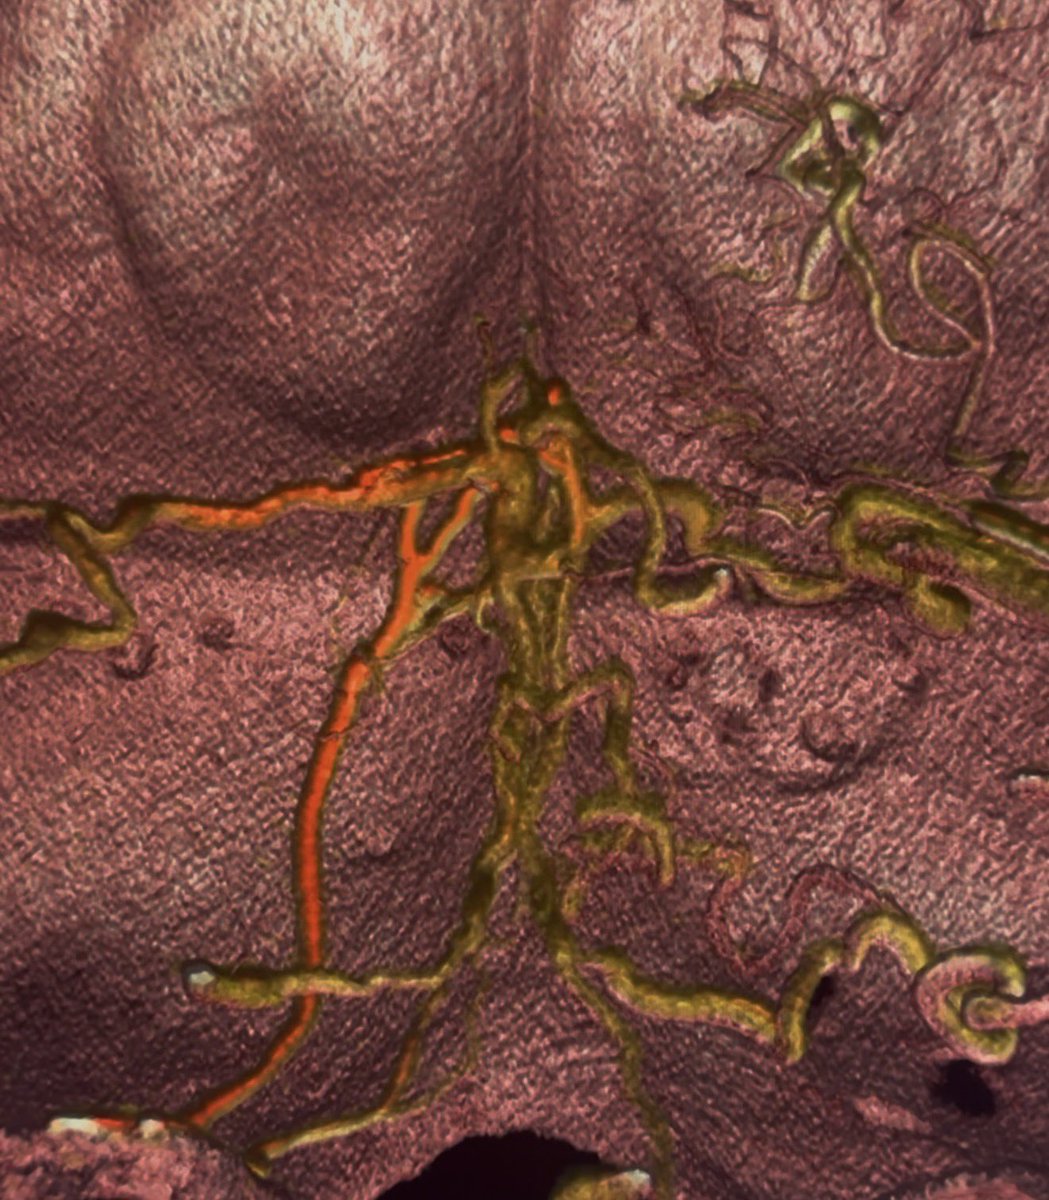

Tumor Workflow: Glomus tympanicum embolization

A case that represents an expansion into a new class of tumor embolization. Planning, imaging, and access from beginning to end.